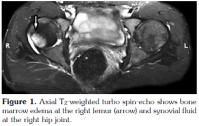

The typical MRI findings of AS are enthesisitis and ankylosis. However, at the very early stage of the disease, synovitis and and subcortical bone marrow edema are important diagnostic features. A number of studies have shown that subchondral bone marrow edema developes as a result of inflammation in various sites such as the sacroiliac joints, femoral heads, and the shoulders.[14-16] The sign of early involvement in AS is subcortical edema. Subcortical edema may be seen at the femoral head, symphisis pubis, and other sites of enthesis (Figure 1, 2). Histological studies have shown that the bone marrow edema in AS is in correlation with osteitis.[17] The femoral head bone marrow edema in AS differs from the diffuse form seen in septic arthritis, and it is more focal, frequently encountered in tendinous and ligamentous insertion sites. A similar pattern was present in the cases of our study (Figure 3). In one study, it was reported that 23% of cases with juvenile AS demonstrated subcortical edema at the symphisis pubis.[17] In our study, no bone marrow edema was encountered at the sites of the symphisis pubis of the patients. This fact may be due to the limited number of the patients enlisted in our study, and also to the difference in the patient age groups between our study and the study mentioned above.

The site of insertion of the tendons, ligaments, joint capsules, and the fascia is known as the enthesis.[18,18] While ultrasonography can only detect soft tissue alterations, MRI can also demonstrate intraosseous abnormalities.[20-24] In our patient group, six patients (13%) had bone marrow edema. Three of these patients had bone marrow edema at the acetabulum, and the other three at the lateral aspects of the femoral heads and the tuberculum majus.